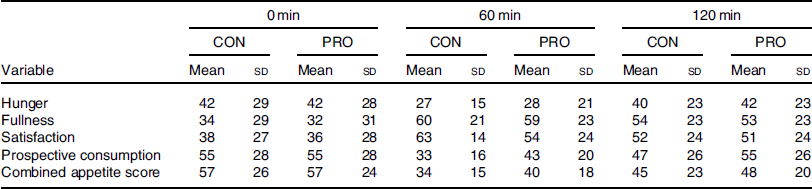

There were no significant differences in any appetite ratings or combined appetite score at pre-breakfast (all P > 0·05, Table 2). There was a main effect of time (P < 0·001, F = 11·411), but neither treatment (P = 0·674, F = 0·185) nor treatment × time interaction (P = 0·681, F = 0·222) for post-prandial combined appetite score. Further, there was a main effect of time (P < 0·03), but neither treatment nor treatment × time interaction (all P > 0·05), for hunger, fullness, satisfaction and prospective consumption during the post-prandial period. There was no difference in volitional energy intake (P = 0·736) in CON (7230 (sd 2849) kJ) compared with PRO (6971 (sd 3205) kJ).

Table 2. Pre-breakfast (0 min) and post-prandial (60, 120 min) subjective appetite responses*

(Mean values and standard deviations)

CON, control; PRO, protein.

* All variables demonstrated a main effect of time (P < 0·03).